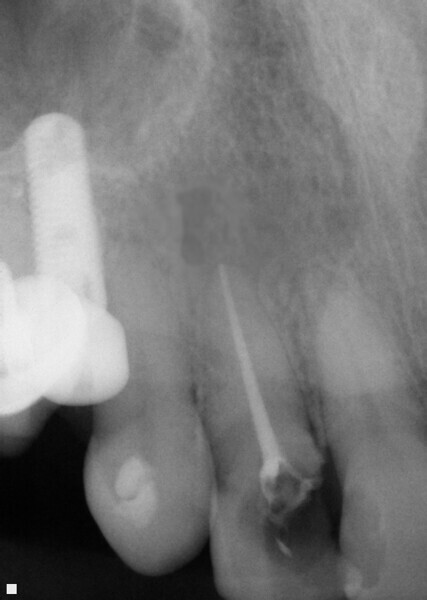

Fig. 10: Tooth 7 presented with large portion of the MBLI missing on tooth with pulpal involvement as evidenced by a moderate periapical area.

Fig. 12: Final obturation following instrumentation of tooth 7 with ExactTaperH DC files and resolution of the apical area utilizing Vitapex as an intracanal medicament between appointments.